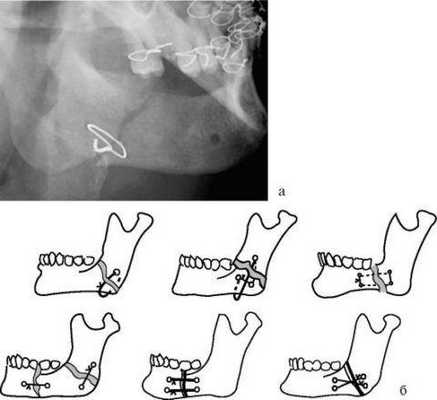

Остеотомия нижней челюсти предусматривает костные разрезы за коренными зубами вдоль челюсти вниз, чтобы нижняя челюсть могла двигаться как единое целое. В результате такой манипуляции нижняя челюсть, с помощью титановой пластины, плавно перемещается на новое место.

Металлические скобы с заданными физическими свойствами

Никель-титановые скобы легко деформируются при пониженных температурах. При попадании этих элементов в комнатные условия скоба возвращается в свое первоначальное положение. Особенно актуален этот остеосинтез при переломе угла нижней челюсти.

Во время операции скобу охлаждают химическим способом и устанавливают в заранее подготовленные костные отверстия. После поднятия температуры тела происходит аппаратная иммобилизация сломанной челюсти.

Спицы Киршнера

В этом случае врач вводит в костные фрагменты специальные металлические спицы посредством бормашины или хирургической дрели. Спицы в челюсть должны проникать на 2-3 см.

Данная малоинвазивная методика терапии переломов создает минимальный уровень дискомфорта для пациента.